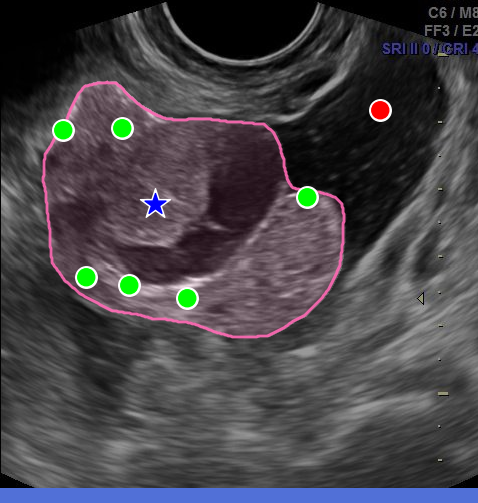

However, in the medical domain, overlapping structures, blurred boundaries, and heuristically defined contours undermine the specificity of point prompts, forcing annotators to rely on more descriptive prompts such as bounding boxes or numerous refinement points. In practice, point prompts trap users in a greedy correction loop: an initial click yields an imprecise mask, which is refined iteratively with new points, each patching local errors instead of working toward a coherent description of the instance as a whole (Fig. 2(a)). Worse, additional refinements can introduce new errors, as the instance identity is gradually established rather than defined upfront. Bounding boxes address identity more directly, but they only constrain the region of interest, leaving the model to infer boundaries with little guidance. They are also cognitively inefficient to draw, as annotators must rely on mental imagery to locate the object’s extremities and position box corners that are not visually anchored, which slows annotation [papadopoulos2017extreme].

A natural alternative is to mark these extremities directly. The extreme points method [papadopoulos2017extreme] asks annotators to click the top-, bottom-, left-, and right-most points of an instance (Fig. 2ii). This bypasses the need to manually place box corners, as they can be computed automatically, while also providing richer information through four boundary points anchored on the object itself. In their daily practice, clinicians rely on a related but distinct convention: to measure structures in ultrasound, they mark the endpoints of the major and minor axes, a simple gesture that encodes geometry, orientation, and extent (Fig. 2iii). We refer to these as the major/minor points. Both 4-points strategies are fast, intuitive, and better capture instance identity, yet SAM-like models have not been adapted to exploit them.

Across eight datasets in ultrasound and surgical endoscopy, S4M achieves consistent gains of +3.42 mIoU over a strong specialist SAM baseline at equal prompt budget (Fig. 2iv). Importantly, it does so while reducing the cognitive load of annotation: by replacing iterative error-finding and correction with more informative 4-point prompts upfront, S4M makes the process faster and less demanding. As it modifies only the prompt encoding stage, the approach remains fully compatible with standard box, region-based, refinement prompts, and adaptable to other SAM-based designs. Finally, an annotation study with three clinicians demonstrates that major/minor point prompts can be collected efficiently, confirming the practical benefit of the proposed approach.